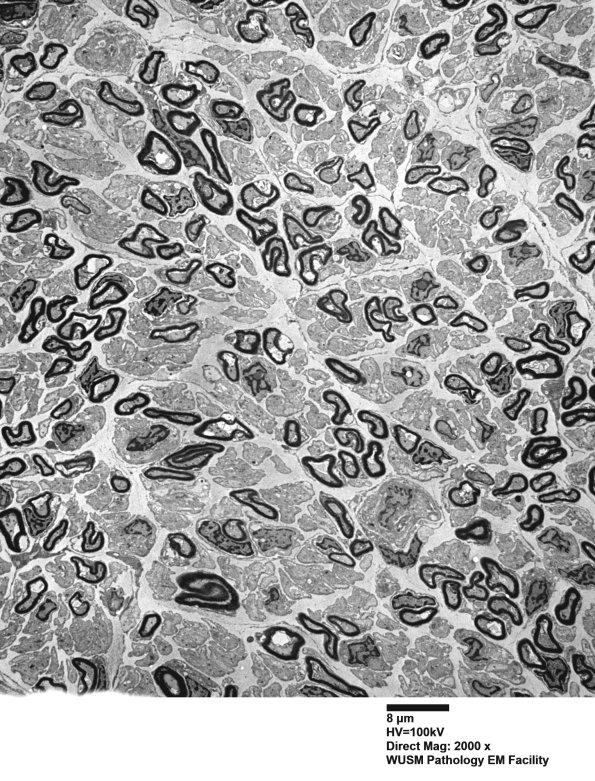

Low magnification ultrastructural images confirm the unimodal myelinated axon population and demonstrate the increased amount of neuropil separating the myelinated axons. (electron micrographs)